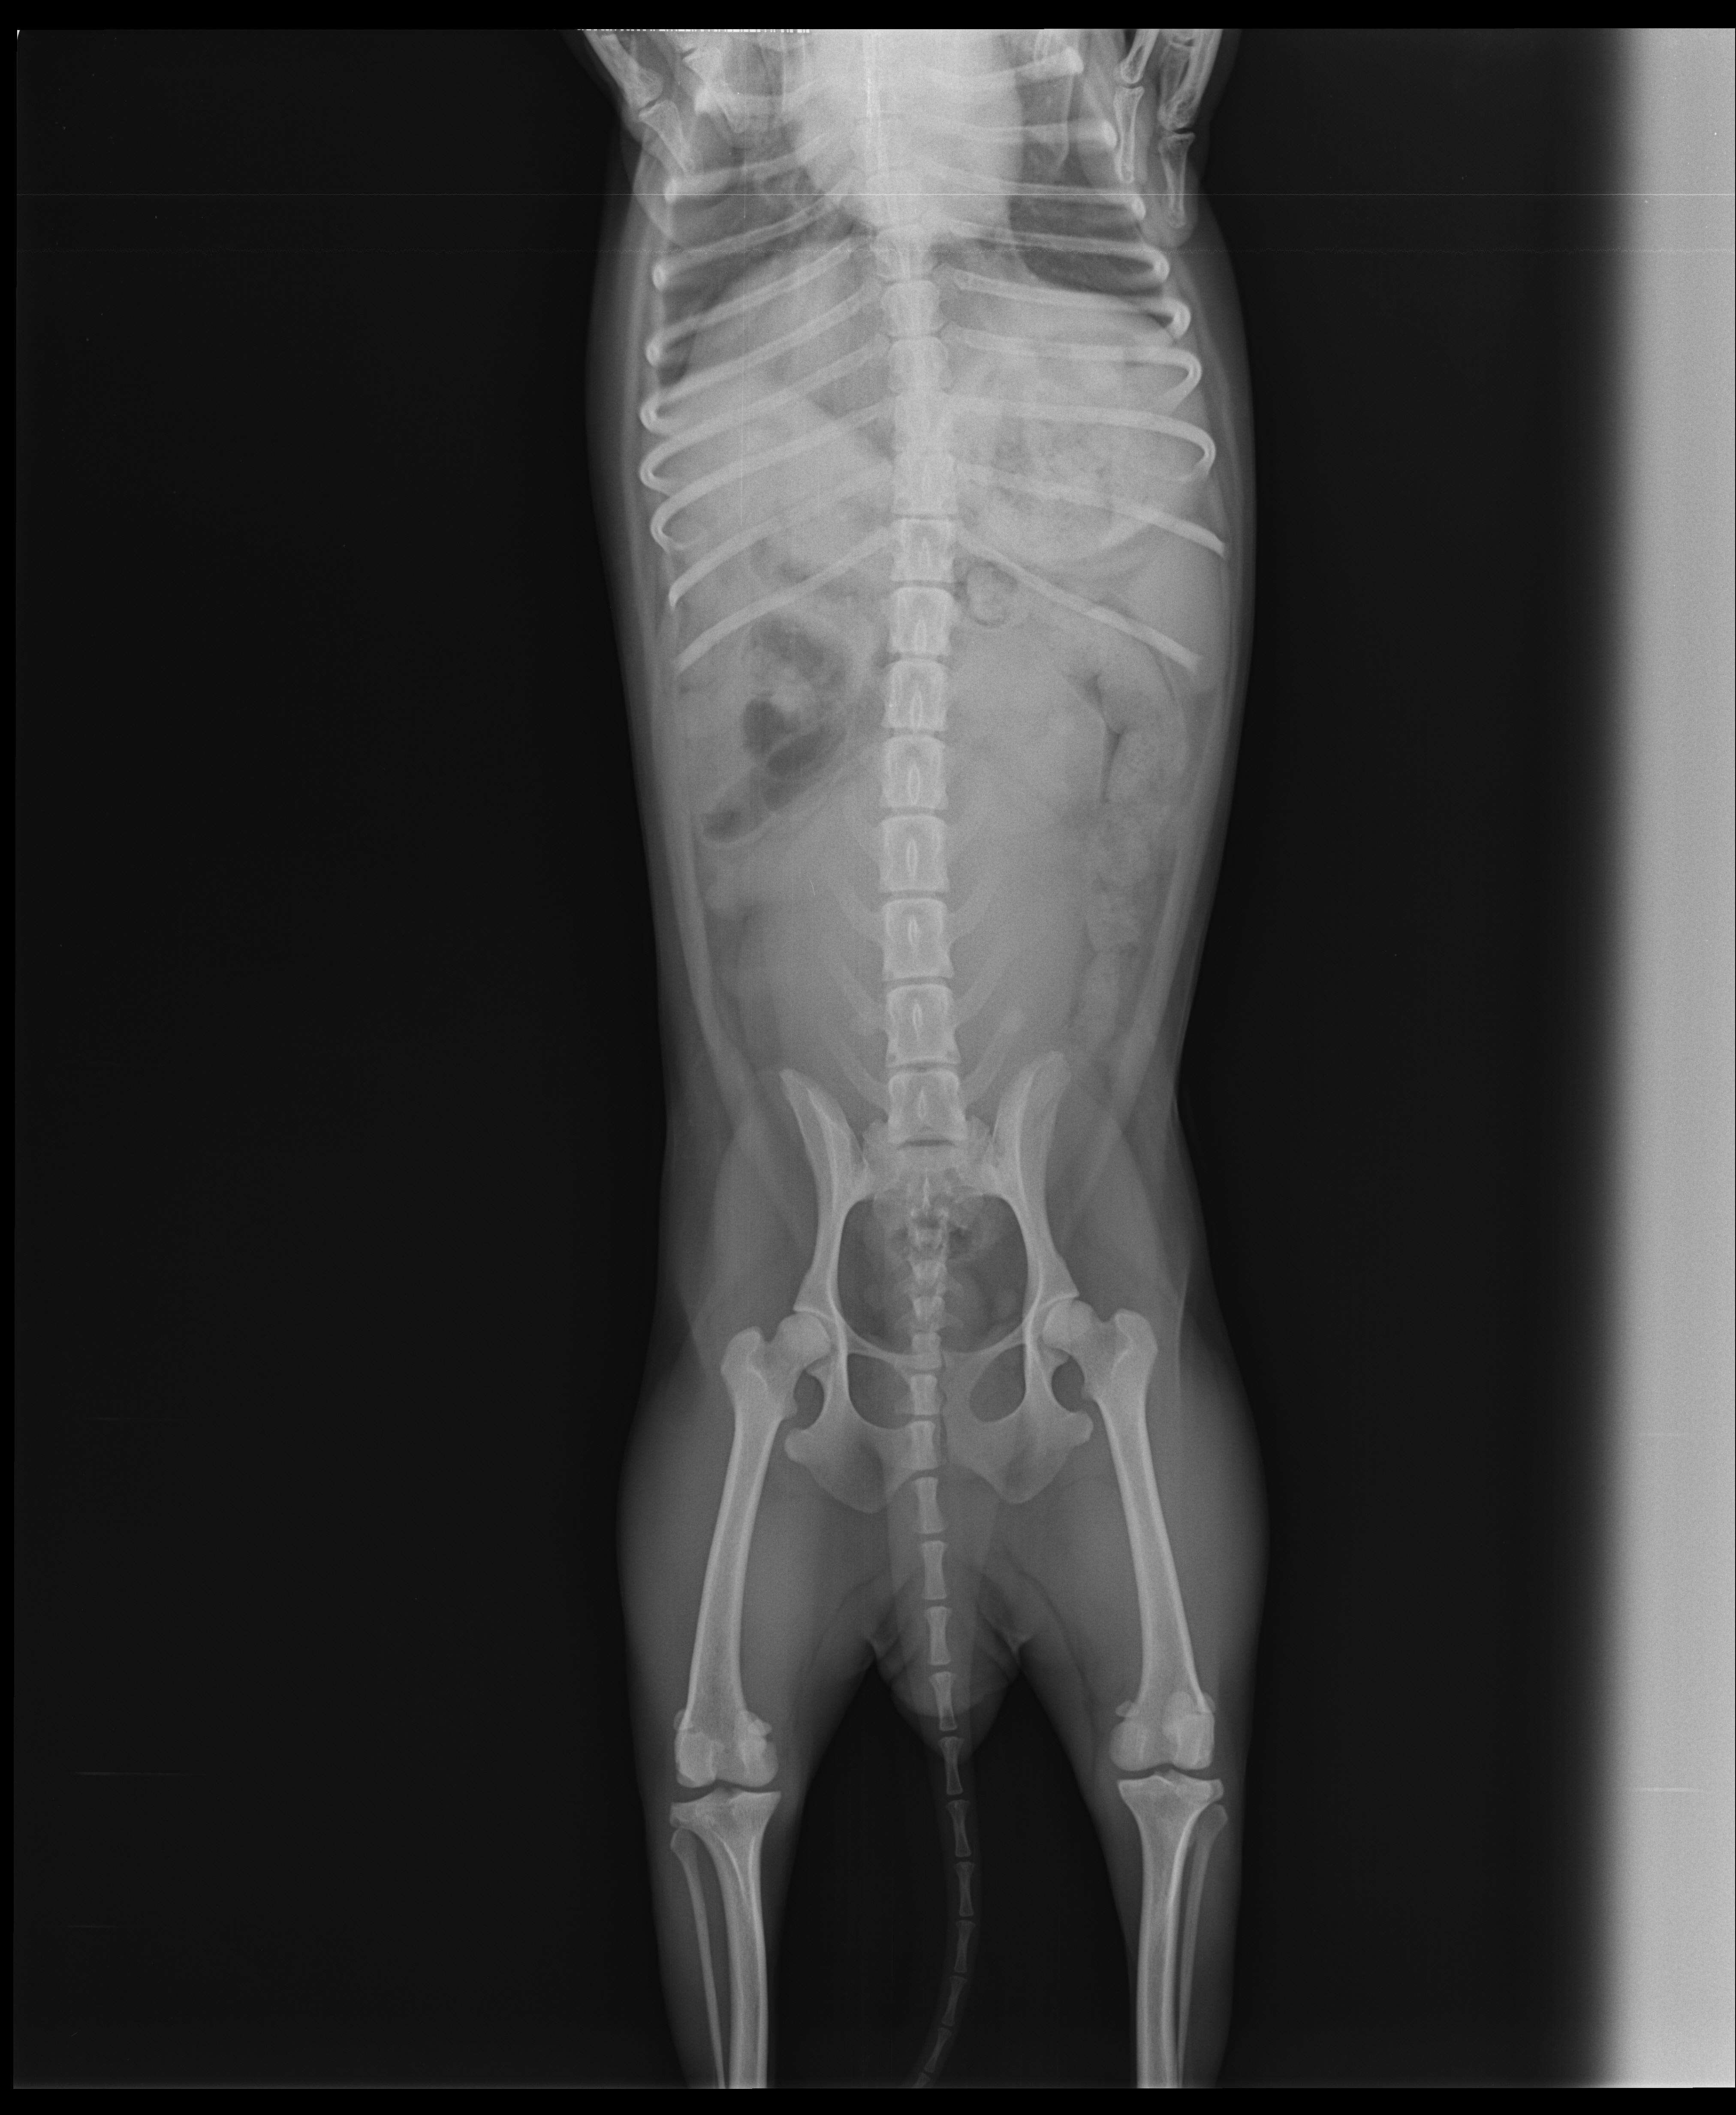

Pet's info: Dog | German Pinscher | Female | unspayed | 4 years and 7 months old | 9 lbs

4 years old female Pinscher. Since two days, she hasn't use rear left leg. Its happen suddenly. Our vet start to vitamin B, pain killer and cortisone. Also her appetite is fine. If you wish, i can sent the videos of her.

As there is no fractures, it's likely to be either a knee cap injury (patelar luxation) or a ligament condition (cruciate ligament tare). you should have the xrays sent to a radiology or orthopedic specialist, she will probably need to have a surgery done on that leg.